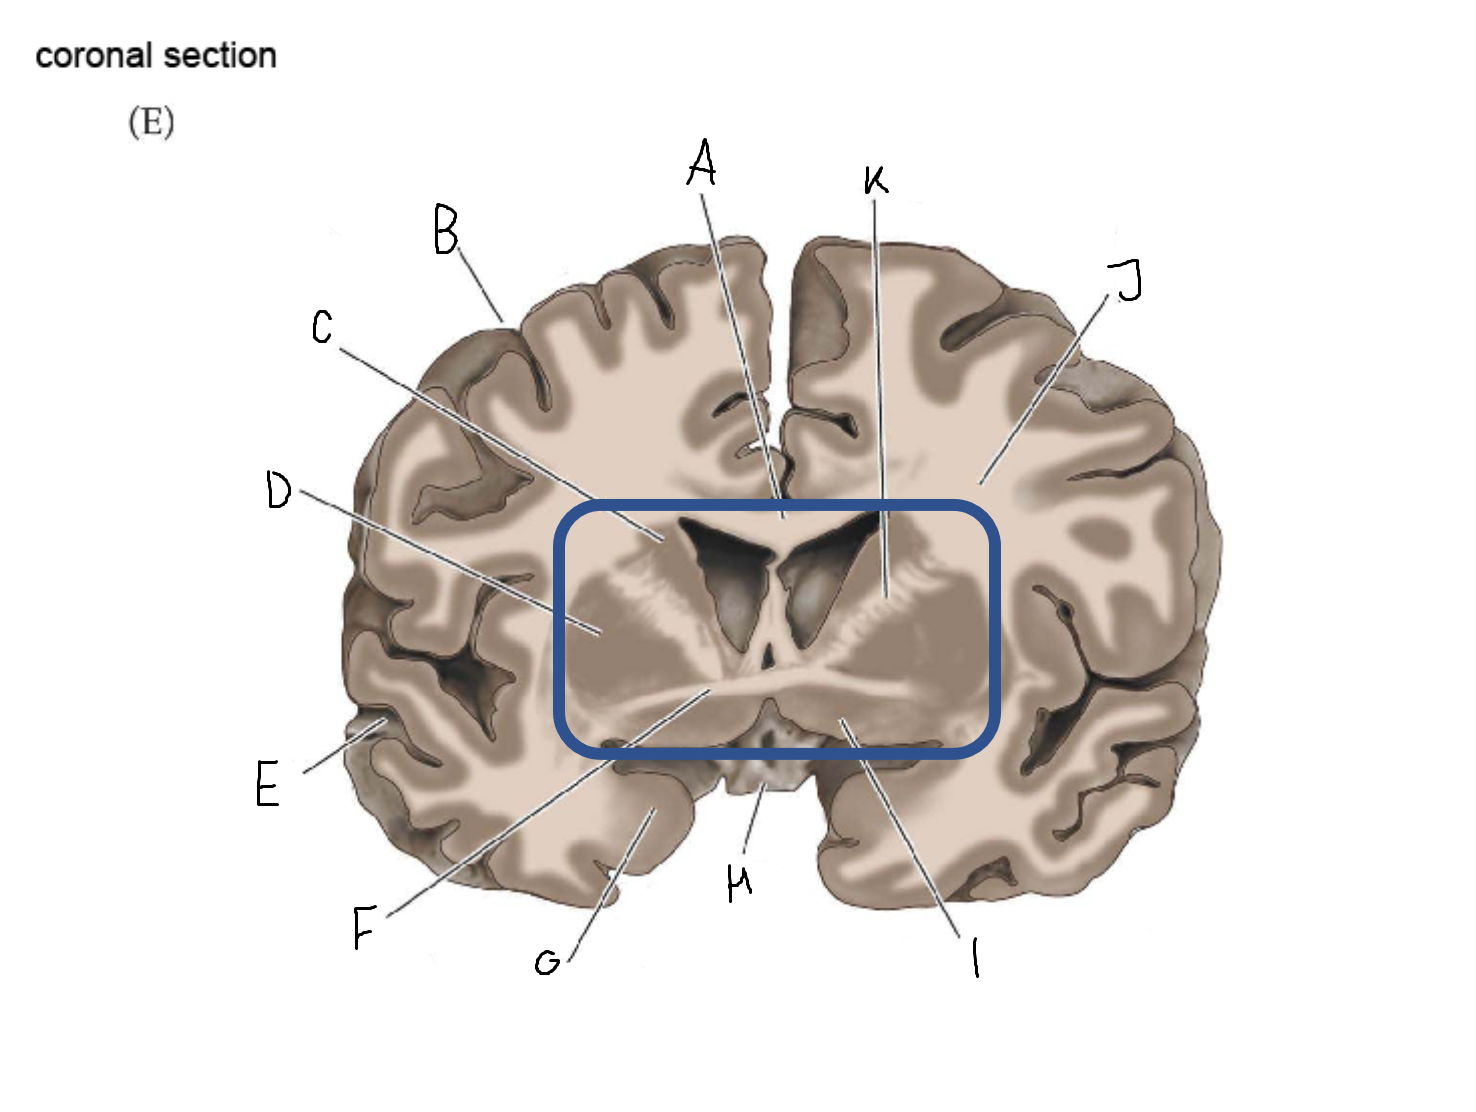

B

anterior horn of lateral ventricle

C

head of caudate nucleus

D

internal capsule (anterior limb)

E

putamen

F

globus pallidus

G

Thalamus

H

External capsule

I

internal capsule (posterior limb)

J

tail of caudate nucleus